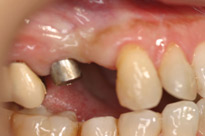

切開をせずインプラントを埋入します。 |

1週間後です。切開してないので歯肉の治りも早いです。 |